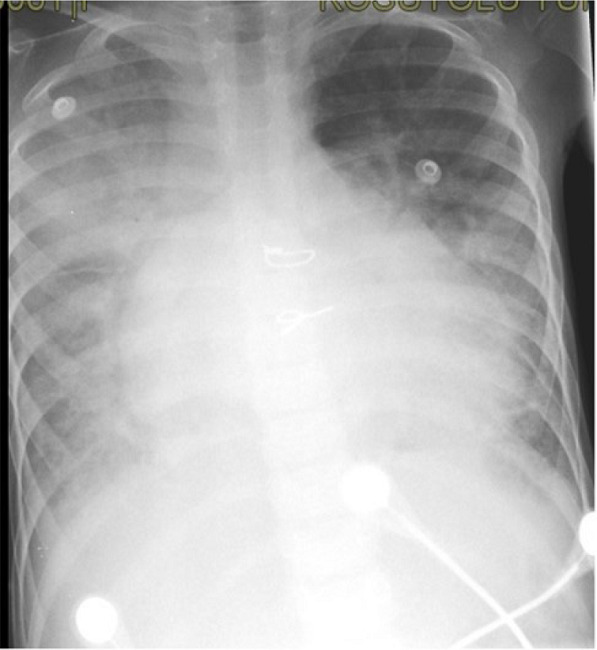

A six-year-old girl with dilated CMP, who was admitted to the emergency room with symptoms of heart failure and fever, was hospitalized. The patient’s COVID-19 RT-PCR test was positive, and widespread infiltrations were detected in her tele-imaging (Figure 2). On the second day after the patient was hospitalized, her general condition deteriorated, and eventually, she died.

Case 2